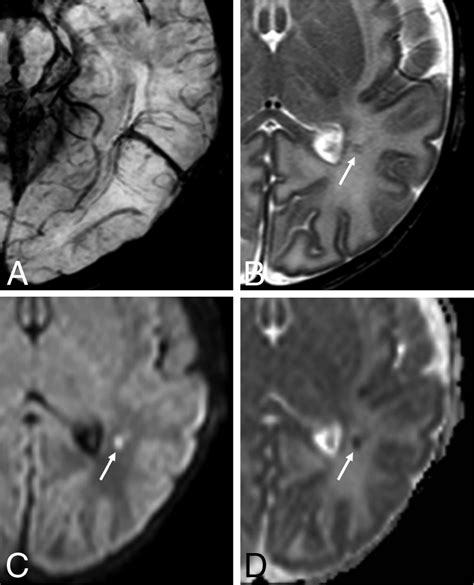

Diagnosing a DVA typically involves imaging studies, such as magnetic resonance imaging (MRI) or computed tomography (CT) scans. These imaging techniques can reveal the characteristic appearance of DVAs, which include:

• Abnormal venous channels

• Dilated venous structures

• Caput medusae appearance, where the venous channels radiate outward like the head of Medusa

In some cases, additional imaging studies, such as angiography, may be performed to better visualize the venous drainage patterns and rule out other vascular malformations.